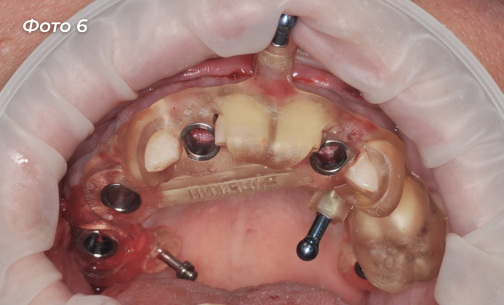

Был изготовлен хирургический шаблон для установки имплантов (Фото 5, 6).